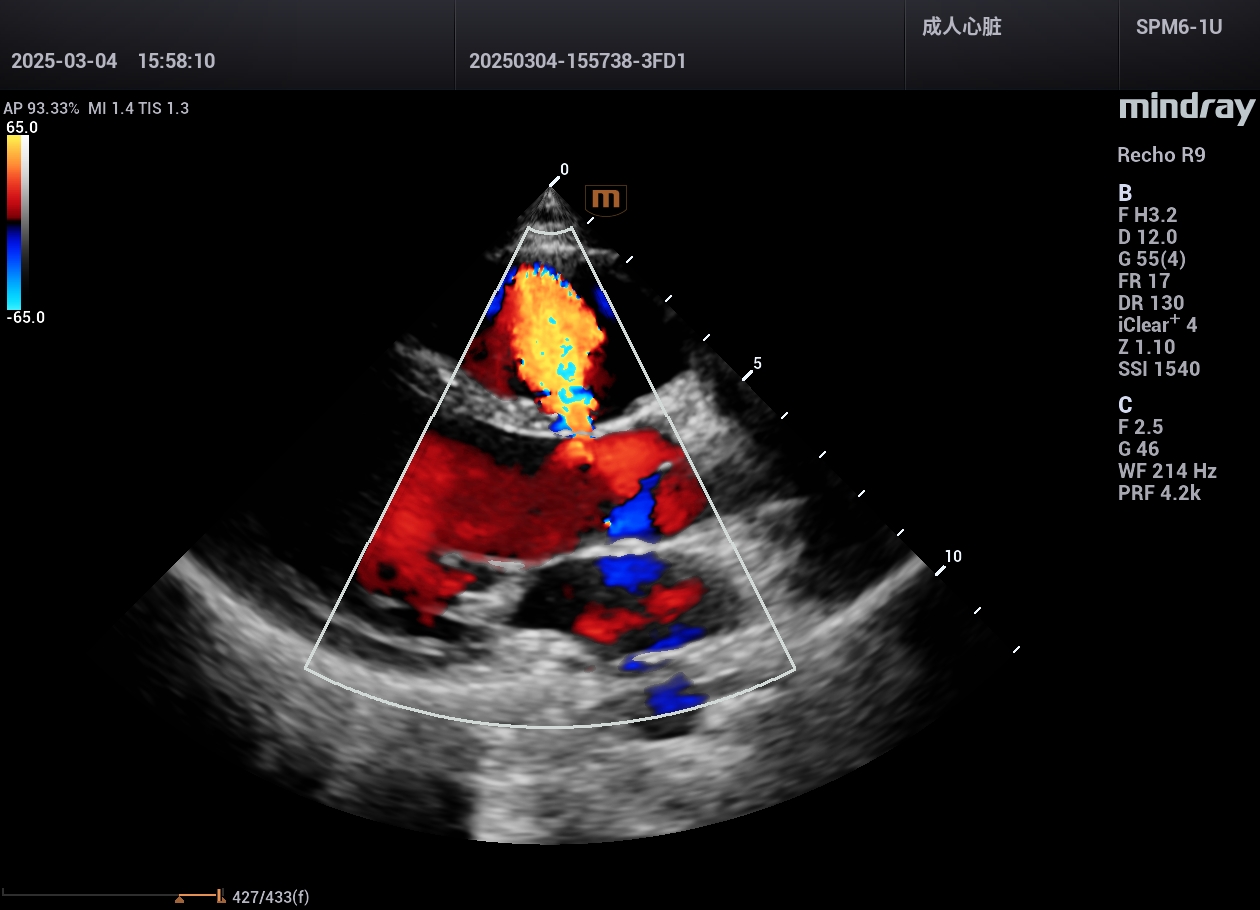

先心病,室间隔缺损,干下型,广西区人民医院医院超声科,2025年

先心病,室间隔缺损,广西区人民医院医院超声科,2025年